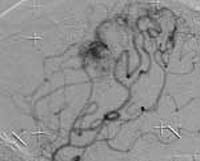

<³úµ¿¸Æ·ù>

<¼ö¼úÀü>

<¼ö¼úÈÄ>

ÀǽÄÀúÇϸ¦

ÁÖ¼Ò·Î ³»¿øÇÑ È¯ÀÚÀÇ Ç÷°üÃÔ¿µ¼Ò°ßÀ¸·Î

³ú±âÀúµ¿¸ÆÀÇ °Å´ë µ¿¸Æ·ù°¡ º¸À̰í ÀÖÀ¸¸ç±¹¼Ò¸¶ÃëÇÏ¿¡¼

³úÇ÷°ü³» ¼ö¼ú·Î µ¿¸Æ·ù³» ÄÚÀÏÀÌ »ðÀÔµÈ

¼Ò°ß

<³»°æµ¿¸ÆÇùÂø>

¿ìÃø Æí¸¶ºñ¸¦ ÁÖ¼Ò·Î ³»¿øÇÑ È¯ÀÚÀÇ

°æµ¿¸Æ doppler ¼Ò°ß°ú Ç÷°üÃÔ¿µ¼ú ¼Ò°ß(ÁÂÃø

³»°æµ¿¸ÆÀÇ ½ÉÇÑ ÇùÂøÀÌ º¸À̰í ÀÖ´Ù)

ÁÂ) °æµ¿¸Æ È®Àå¼ú ½Ã¼úÀå¸é

¿ì)

°æµ¿¸Æ È®Àå¼ú ¹× ½ºÅÙÆ® »ðÀÔ¼ú ½ÃÇàÈÄ

(Á¼¾ÆÁ®

ÀÖ¾ú´ø ³»°æµ¿¸ÆÀÇ È®ÀåµÇ¾î ÀÖ´Ù.) |